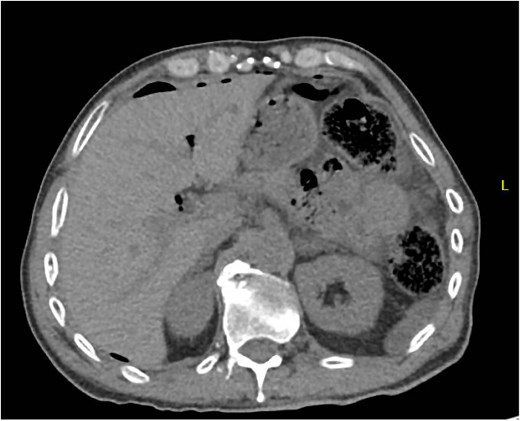

A 44 year old male presented to the hospital with left lower quadrant abdominal pain and diarrhea. Initial workup showed sigmoid diverticulitis with a small pericolic abscess (<3 cm) (Fig. 3a). The patient was admitted to the hospital and treated with bowel rest and IV antibiotics. Unfortunately, the patient failed nonoperative management and repeat CT imaging showed increased extraluminal air (Fig. 3b). He was taken to the operating room on hospital Day 8. Intra-operatively, the patient was found to have purulent peritonitis, left colon diverticulitis, and associated pericolic abscess. He underwent a left colectomy with primary anastomosis. Fluid cultures were obtained. The fascia was closed with #1 non looped PDS and interrupted figure of eight stitches. The umbilicus was approximated with sutures, and a negative pressure subcutaneous wound vac was placed to the midline laparotomy incision and kept on continuous suction at -125 mm Hg. The first wound vac change occurred on POD 2 (Fig. 4a) and then the wound was changed every other day similar to Patient A. DPC was performed on POD 8 (Fig. 4b). The patient’s hospital course was complicated by a prolonged postoperative ileus requiring TPN and an upper GI bleed that was treated medically with PPI therapy. The patient did also have a postoperative abscess that was treated with an IR-guided drain and prolonged antibiotic therapy until POD 20. The patient’s stay was further prolonged due to his initial need for a nursing facility at discharge- he was from out of state and his insurance was not accepted at any facilities. He was ultimately discharged to home on POD 20. The patient was then seen in the office 15 days after discharge and 27 days after DPC on POD 35. The midline incision was healing well and was without any signs of SSI (Fig. 4c).

Patient B. a. Initial CT abdomen and pelvis showing acute diverticulitis with small adjacent abscess. b. Repeat CT abdomen and pelvis with worsening complicated diverticulitis.